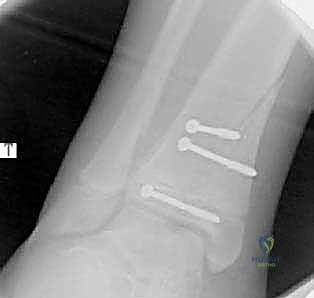

- الأشعة السينية (X-rays): هي الخطوة الأولى والأساسية. يتم التقاط صور من زوايا متعددة (أمامية، جانبية، ومائلة) لتقييم الكسر.

- الأشعة المقطعية ثلاثية الأبعاد (3D CT Scan): تُعد ضرورة حتمية في حالات كسور تيلوكس والكسور ثلاثية المستويات، أو أي كسر يمتد داخل المفصل. توفر الأشعة المقطعية خريطة دقيقة لحجم القطع العظمية ومقدار التباعد (Displacement)، مما يساعد في التخطيط الجراحي المسبق.

ثانياً: التدخل الجراحي (الرد المفتوح والتثبيت الداخلي - ORIF)

يصبح التدخل الجراحي ضرورة طبية لا مفر منها تحت إشراف الأستاذ الدكتور محمد هطيف في الحالات التالية:

* جميع كسور سالتر-هاريس من النوع الثالث والرابع إذا كان هناك تباعد أكثر من 2 ملم في السطح المفصلي.

* كسور تيلوكس والكسور ثلاثية المستويات ذات الانزياح الواضح.

الدليل الجراحي التفصيلي: خطوة بخطوة مع الأستاذ الدكتور محمد هطيف

عندما يقرر الأستاذ الدكتور محمد هطيف إجراء الجراحة، فإن العملية تتم وفق أعلى المعايير العالمية المتبعة في أعرق المستشفيات. الجراحة ليست مجرد "تثبيت بمسامير"، بل هي فن هندسي وطبي متكامل لحماية مستقبل الطفل.

يقوم الدكتور هطيف بعمل شق جراحي دقيق بأقل تداخل ممكن (Minimally Invasive) للوصول إلى موقع الكسر. يعتمد مكان الشق (أمامي، جانبي، أو إنسي) على نوع الكسر. يتم إبعاد الأوتار والأعصاب والأوعية الدموية بحذر شديد باستخدام تقنيات الجراحة الميكروسكوبية.

3. إزالة الأنسجة المتداخلة والرد التشريحي (Debridement & Reduction)

هذه هي الخطوة الأهم. كما ذكرنا سابقاً، غالباً ما يتداخل السمحاق (Periosteum) داخل خط الكسر. يقوم الدكتور هطيف بإزالة هذا السمحاق المتداخل برفق، وتنظيف موقع الكسر من أي جلطات دموية أو شظايا عظمية صغيرة. بمجرد تنظيف الموقع، يتم إعادة القطع العظمية إلى مكانها الطبيعي بد